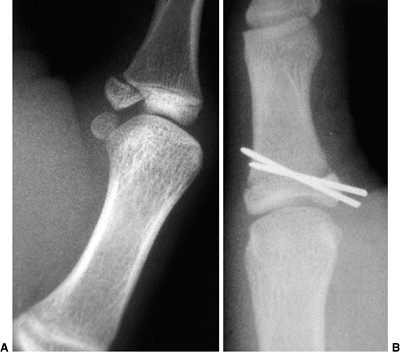

advanced grade III), development of a false glenoid (grade IV) (Fig. 23.6),

![]() |

Figure 23.6 A:

Schematic showing the method of measuring the glenoscapular angle (glenoid vision) and the percentage of posterior subluxation of the humeral head. To measure the glenoscapular angle, a line is drawn parallel to the scapula and a second line is drawn tangential to the joint. The second line connects the anterior and posterior margins of the glenoid.The cartilaginous margins are used on magnetic resonance images. The osseous margins are used on computed tomographic scans. The intersecting line connects the center point of the first line (approximately the middle of the glenoid fossa) and the medial aspect of the scapula. The angle in the posterior medial quadrant is measured with a goniometer (arrow), and 90 degrees is then subtracted from this measurement to determine the glenoid version. The percentage of posterior subluxation is measured by defining the percentage of the humeral head that is anterior to the same scapular line. The greatest circumference of the head is measured as the distance from the scapular line to the anterior portion of the head. This ratio [the distance to the anterior aspect of the humeral head (AB) divided by the circumference of the humeral head (AC), multiplied by 100] is the percentage of subluxation. B: Magnetic resonance imaging of a type IV deformity with posterior humeral head subluxation and the development of a false glenoid. The glenoid is markedly retroverted. The contralateral glenohumeral joint is normal for age. |